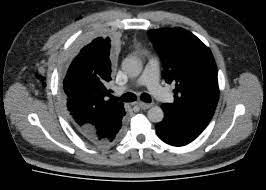

Eliminación temprana mínimamente invasiva de hemorragia intracerebral

En los pacientes en quienes la cirugía se pudo realizar dentro de las 24 horas posteriores a una hemorragia intracerebral aguda, la evacuación mínimamente invasiva del hematoma produjo mejores resultados funcionales a los 180 días que el  tratamiento médico basado en guías. El efecto de la cirugía parece atribuirse a la intervención de las hemorragias lobares. New England Journal of Medicine, 10 de abril de 2024.